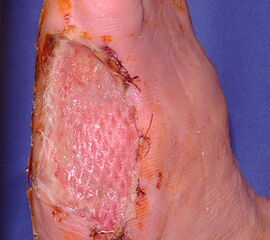

Die Knochenenden müssen so gestaltet werden, dass sie keinen Druck auf die Haut aus­üben können. Wenn sich die Wundränder nicht durch Nähte verschließen lassen (z.B. nach Infektion), wird in den nicht belasteten Regionen eine Spalthautdeckung vorgenommen (Abb. 28, 29), wenn eine infektfreie Granulation vorliegt.